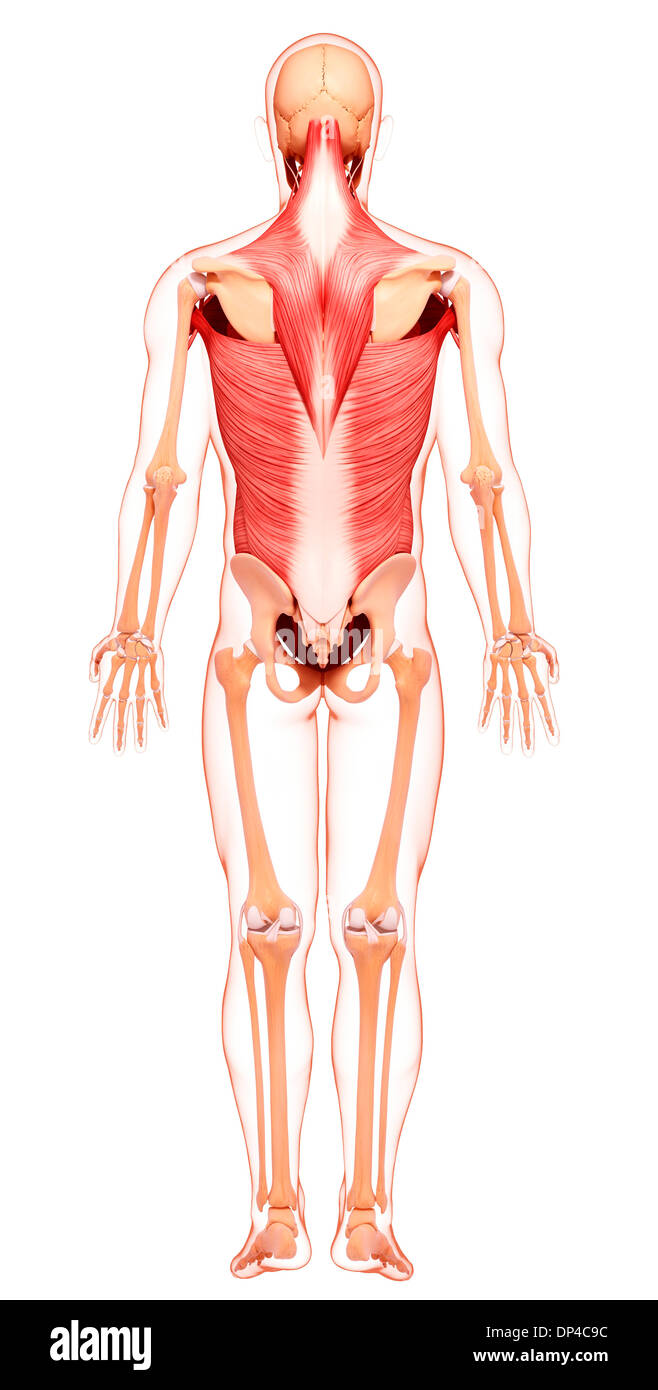

Musculature, artwork Banque D'Imageshttps://www.alamyimages.fr/image-license-details/?v=1https://www.alamyimages.fr/musculature-artwork-image65229644.html

Musculature, artwork Banque D'Imageshttps://www.alamyimages.fr/image-license-details/?v=1https://www.alamyimages.fr/musculature-artwork-image65229644.htmlRFDP3D24–Musculature, artwork